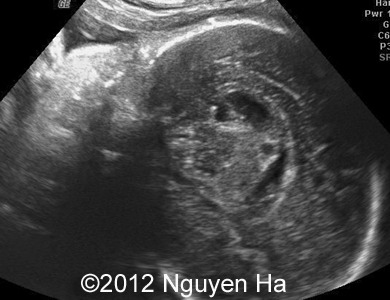

A 30-year-old woman (G1P0), with unremarkable family history, presented to our unit at 36 weeks of her pregnancy. She did not undergo any previous screening tests. Our examination (and repeated scan after four days) revealed following findings:

A 30-year-old woman (G1P0), with unremarkable family history, presented to our unit at 36 weeks of her pregnancy. She did not undergo any previous screening tests. Our examination revealed unilateral hypoechoic inhomogeneous mass within cerebral parenchyma. Our initial diagnosis was teratoma, but repeated exam after four days showed structural changes and different echogenicity of the mass and so our final diagnosis was cerebral hemorrhage. The findings were confirmed by MRI scan.

Figure 8-15: 4 days later; image 1-4 suggesting a middle cerebral artery infarction with formation of schizencephaly, no more cortex at the level of the insula.